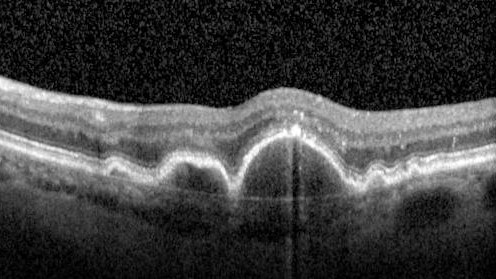

Focal Hyperpigmentation in Dry Age-Related Macular Degeneration

74 year old female with 20/32 vision right eye and 20/25 vision in the left eye. Images show focal hyper-pigmentation which is a risk factor for progression to wet AMD